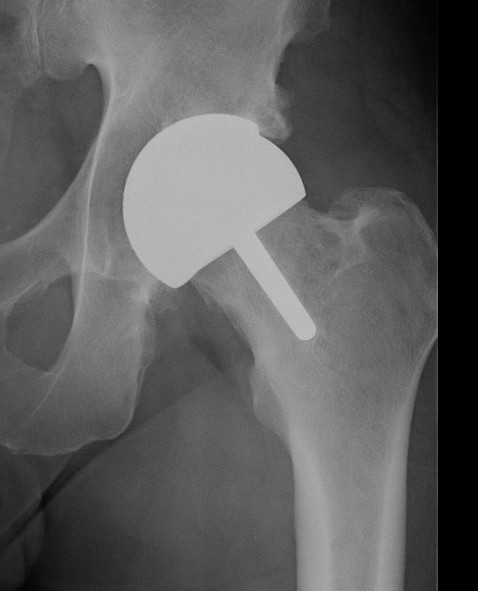

Birmingham hip resurfacing

Concept

Femur - removal of femoral head cartilage and resurfacing with metal

Acetabulum - standard technique

Bearing surface - metal on metal

Birmingham Resurfacing

Oversized head

Varus Femoral Component

Femoral head notching

Open Acetabular Component - may cause point loading and increased metal wear